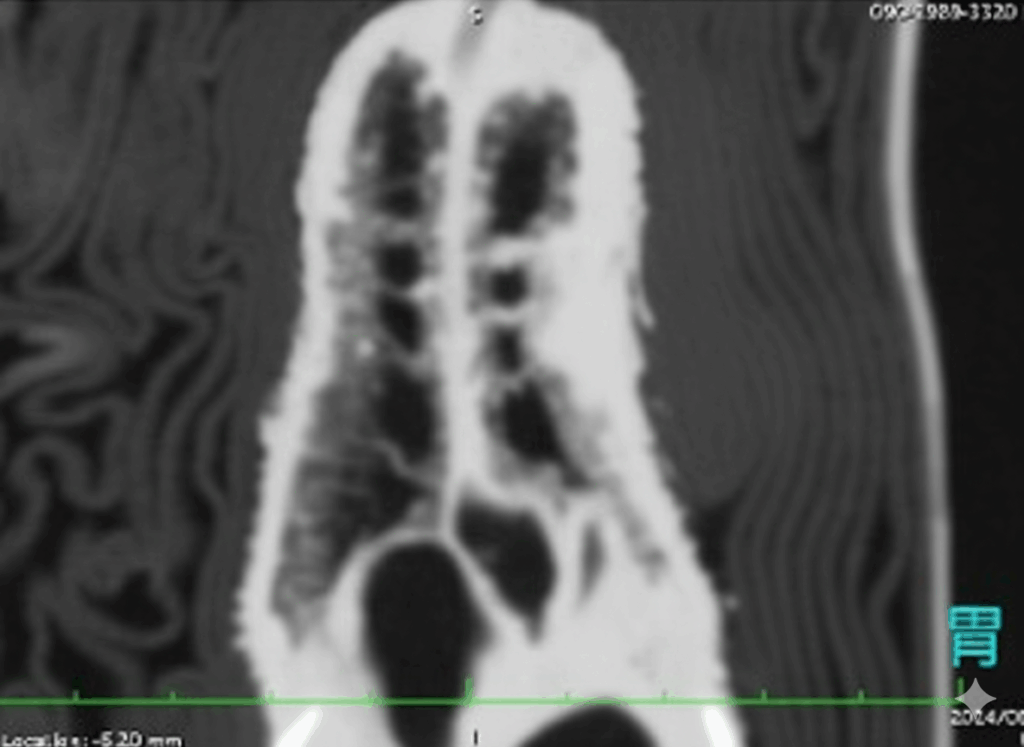

CT検査は、X線では評価が難しい初期病変や、肺実質の詳細な病変(例:微小な膿瘍、真菌症の病巣)を特定する上で、極めて優れた診断情報を提供します。